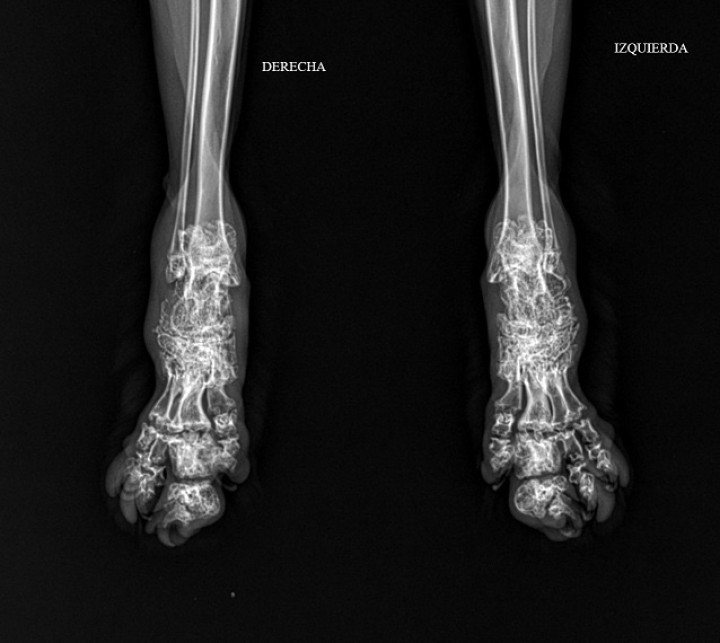

Se realizaron radiografías de ambas extremidades posteriores en proyección mediolateral (Fig. 1).

<p>Proyección dorsoplantar de la parte distal de las extremidades posteriores (<em>pes</em>) del paciente donde se observa acortamiento, deformidad y engrosamiento de tarsos, metatarsos y falanges, así como pérdida de los espacios articulares de dichas zonas.</p>

Figura 5

Proyección dorsoplantar de la parte distal de las extremidades posteriores (pes) del paciente donde se observa acortamiento, deformidad y engrosamiento de tarsos, metatarsos y falanges, así como pérdida de los espacios articulares de dichas zonas.